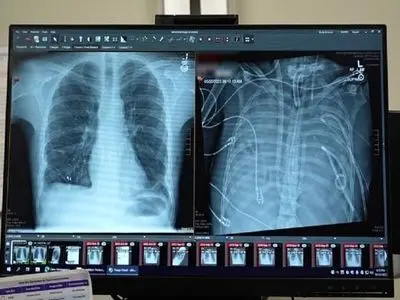

یک مرد ۳۳ ساله بعد از اینکه گروه پزشکی، اعضای بدنش را با یک سیستم ریه مصنوعی خارجی جایگزین کردند که توسعه یافته بود تا او را زنده نگه دارند که بتواند پیوند دو ریه دریافت کند، به مدت ۴۸ ساعت بدون ریههایش زنده ماند.